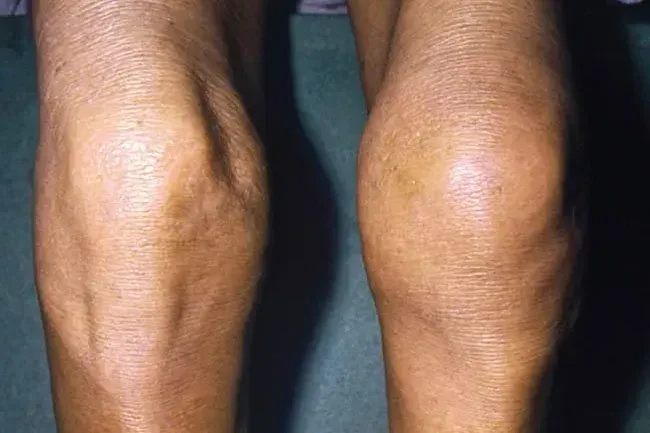

Bursitis

Dette gør dit knæ hævede stift og varmt eller ømt at røre ved normalt, fordi du har overarbejdet det. Tilstanden er også kendt som 'Housemaid's knæ' eller 'præstens knæ', fordi folk med disse job knæler så meget. Det sker, når små fluidfyldte sække kaldet bursa, der hjælper med at dæmpe dit knæled, bliver irriteret og hævet. Du kan have ondt, selv når du hviler.